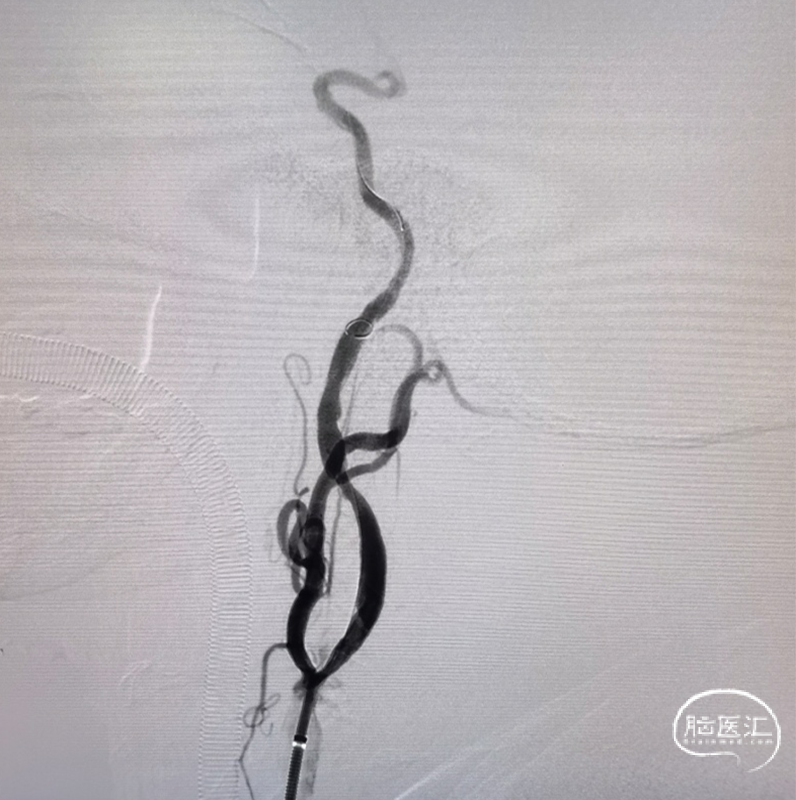

右侧颈总正侧位:见右侧颈内动脉闭塞,颅外血管代偿良好。

左颈总正侧位:左侧颈内动脉闭塞,可见血管残端。

泥鳅导丝+125多功能导管越过颈内动脉起始部闭塞段血管。

6F 115cm中间导管抽吸血栓2次后路图,见大脑中动脉、大脑前动脉闭塞。